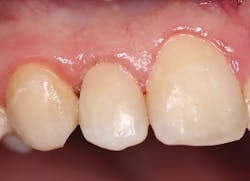

A 20-year-old male presented with numerous class V decalcification lesions, some of which extended through the enamel and required a direct restorative approach (figure 1). After anesthesia was obtained, removal of the caries with a pear-shaped carbide bur (#330 NeoBurr, Microcopy Dental) was completed. An enamel bevel of 2–3 mm with an irregular outline was placed with a 45u flame-shaped diamond (209.6 VF, Premier Dental) to facilitate enamel etching and blending of the composite. The preparation was isolated using a clear Mylar-based matrix (Margin Perfect Matrix). A total-etch technique was employed, followed by the use of a universal bonding agent (Tokuyama Universal Bond, Tokuyama Dental America) according to the manufacturer’s instructions. A single application of Omnichroma was expressed and manipulated with composite instruments and brushes prior to curing with an LED light source for 20 seconds. Once the matrix was removed, finishing was accomplished with 12 fluted spiral-bladed carbide burs (H48L-010, H274-016, Brasseler USA), and final polish was achieved with a series of abrasive cups and points (Astropol, Ivoclar/Vivadent) to a final luster (figure 2).